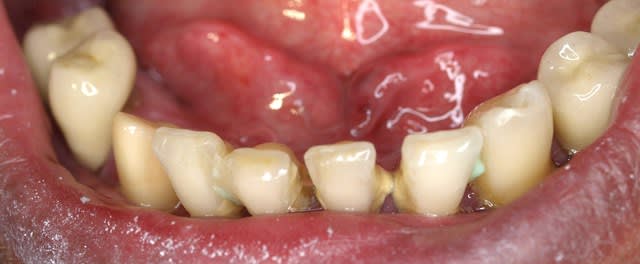

ha ben tiens voila les photo de l'epoque ou je l'ai connu . entre temps il s'est barré voir un aute cd un peu implanto mais pas trop qui lui a viré tout le haut ...

Il reste 45, 35? rien d'autre?